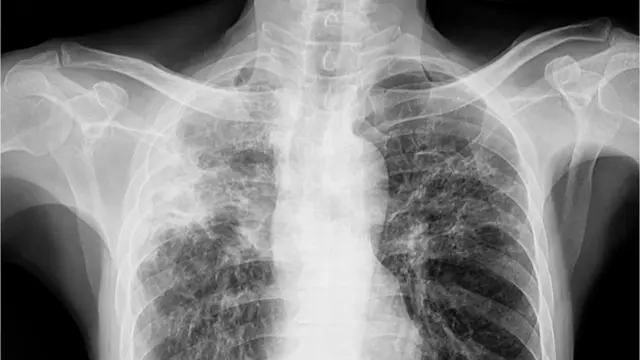

শিশুদের ক্ষেত্রে ফুসফুসের যক্ষ্মা নির্ণয়েও অনেক সময় দেরি হয়। এর একটি কারণ হতে পারে শিশুরা বলতে পারে না, বোঝে না, কফ বের করতে পারে না। অভিভাবকরাও অনেক সময় খেয়াল করতে দেরি করেন।

বড়রা বলতে পারে, কফ ফেলতে পারে, কফের সাথে রক্ত গেলে সেটা বলতে পারে, সেজন্য বড়দের যক্ষ্মা নির্ণয় করা সহজ।

ছবির উৎস, Getty Images

বাচ্চারা কফটা গিলে ফেলে তাই সেটা পেটে চলে যায়। এক্ষেত্রে যক্ষ্মা নির্ণয়ে পাকস্থলীর রস বের করে আনা হয়। অনেক ক্ষেত্রে নমুনা নেয়ার জন্য বাচ্চাকে বমি করানো হয়। কফ গিলে ফেলার কারণে জীবাণু বাচ্চাদের পেটে পাওয়া যায়।

এছাড়া পরিবারে কারো যক্ষ্মা আছে কি না তার ইতিহাস, এক্স-রে, বাচ্চাদের ত্বকে একটি পরীক্ষা করা হয়। কিন্তু শিশুদের শরীর থেকে নমুনা নিলেও জীবাণুর উপস্থিতি বড়দের চেয়ে কম থাকে তাই প্রচলিত পরীক্ষাতেও অনেক সময় ধরা পড়ে না।